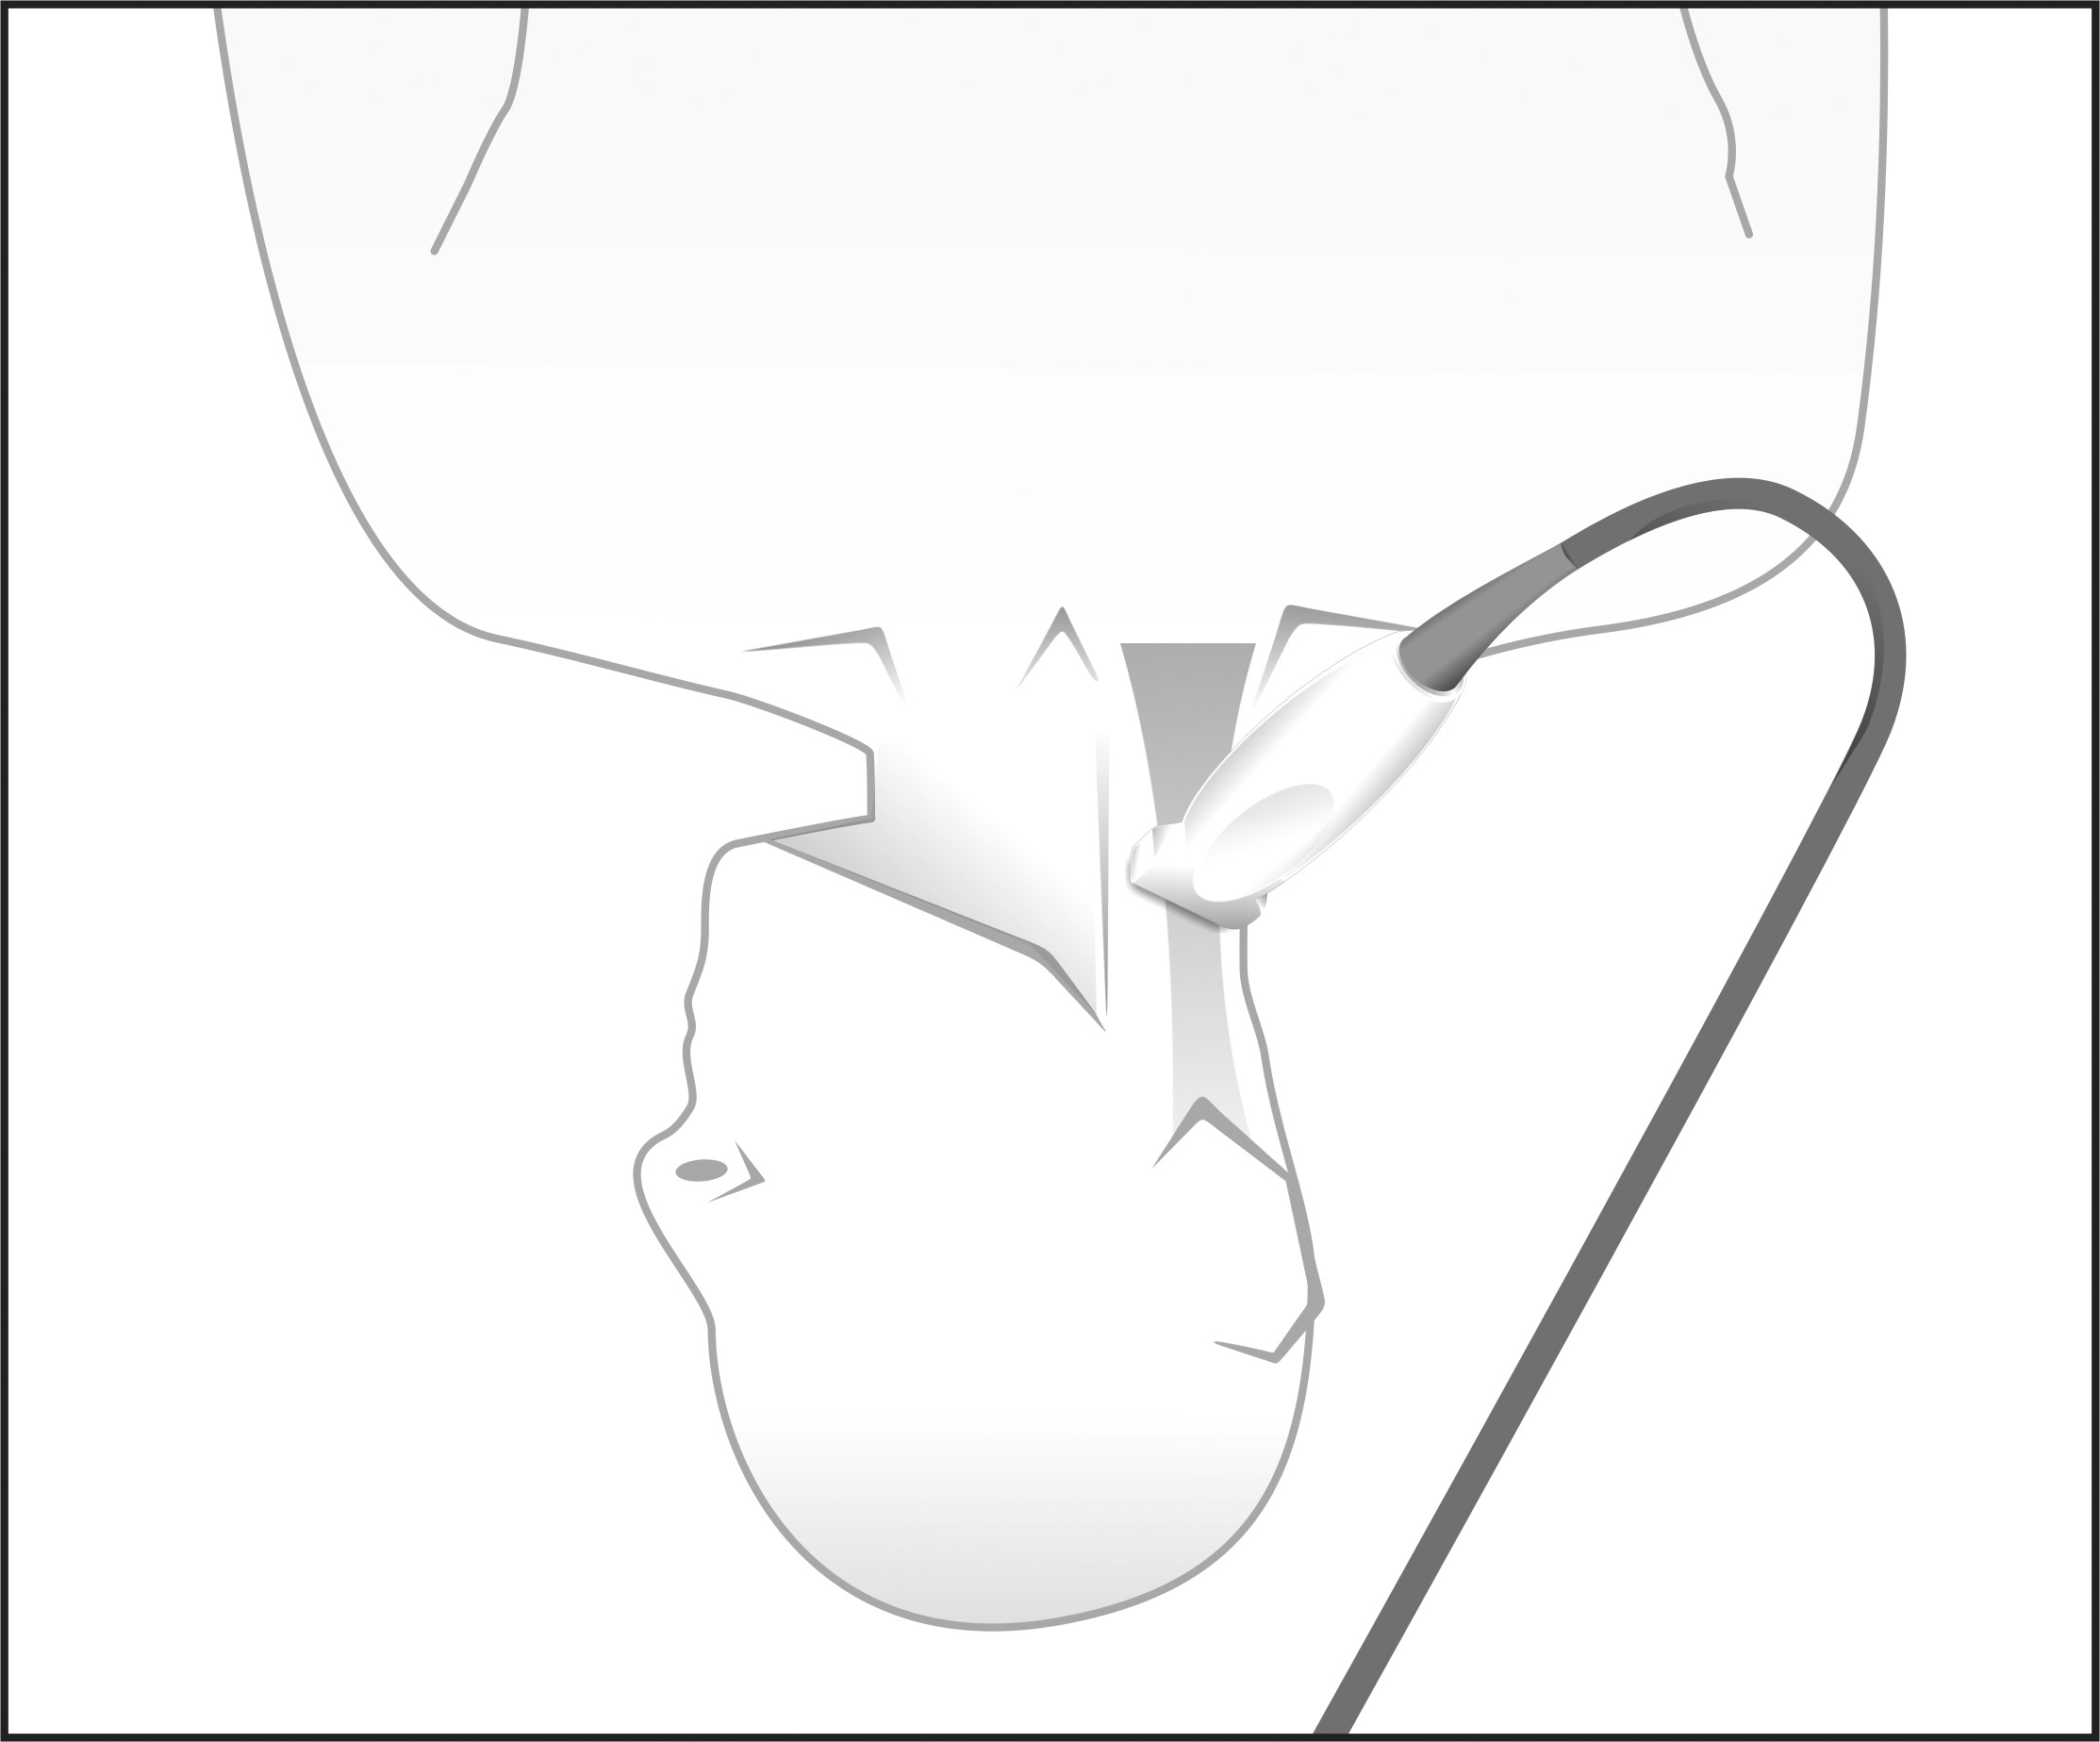

Figura 1.

Colocación del paciente para el examen. La cabeza se gira a la opuesta lado y la sonda está orientada transversalmente, perpendicular al eje de la vasos.

El estudio ecográfico se realizó con el paciente en decúbito supino, con la cabeza en posición neutra y posteriormente en rotación hacia el lado contrario al examinado. Se visualizó transversalmente el tercio proximal del cuello, con un ecógrafo Sonosite 180 o Sonosite EDGE (Sonosite, Bothell, Washington) empleando un transductor lineal de 7.5 mHz, con el punto de referencia del equipo dirigido a la línea media (Figs. 1 y 2). Los estudios fueron almacenados digitalmente para ser analizados posteriormente.